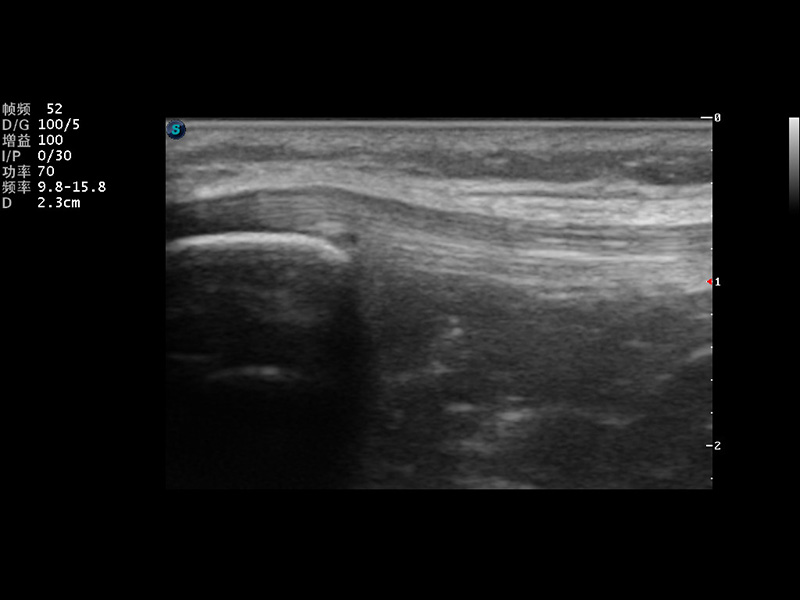

VIS平台设计